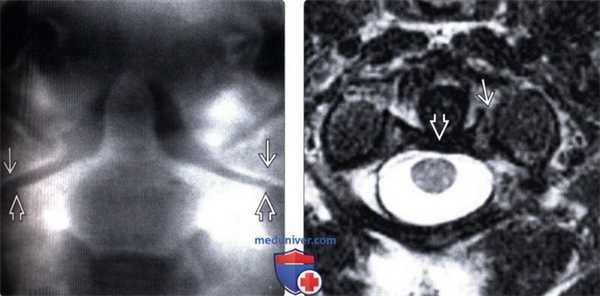

(Слева) КТ, фронтальный срез: расширение суставных щелей атланто-затылочных суставов (АЗС). Небольшие костные фрагменты представляют собой отрывные переломы нижне-медиального края мыщелков затылочной кости. Переломы в области прикрепления связок эквиваленты разрыву этих связок и только усиливают выраженность нестабильности КВС.

(Справа) Т2-ВИ, фронтальная проекция: расширение и гиперинтенсивность сигнала обоих АЗС. Также здесь видно нарушение непрерывности обеих крыловидных связок.